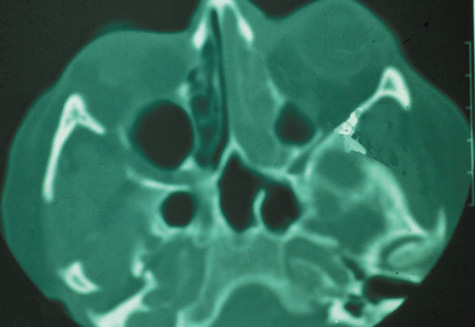

With preseptal inflammation, CT demonstrates soft tissue swelling of the eyelids and tissue adjacent to the orbital septum (Fig. 15). The orbit is not involved, and usually the sinuses do not show evidence of inflammation. The distinction between inflammatory preseptal cellulitis and edema cannot be made.63

Fig. 15. Computed tomography showing preseptal cellulitis of left eye. Note that all swelling is anterior to the orbital septum.